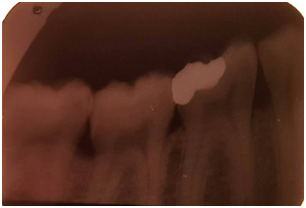

The vitality test revealed a positive response of the 46. The radiological examination showed a large-scale amalgam restoration at a distance from the pulp (Figure 2). After clinical examination, the appropriate treatment option was a ceramic onlay restoring the 46 using the IPS e.max CAD system.

Figure 2 Periapical radio on the 46: a large-scale amalgam.